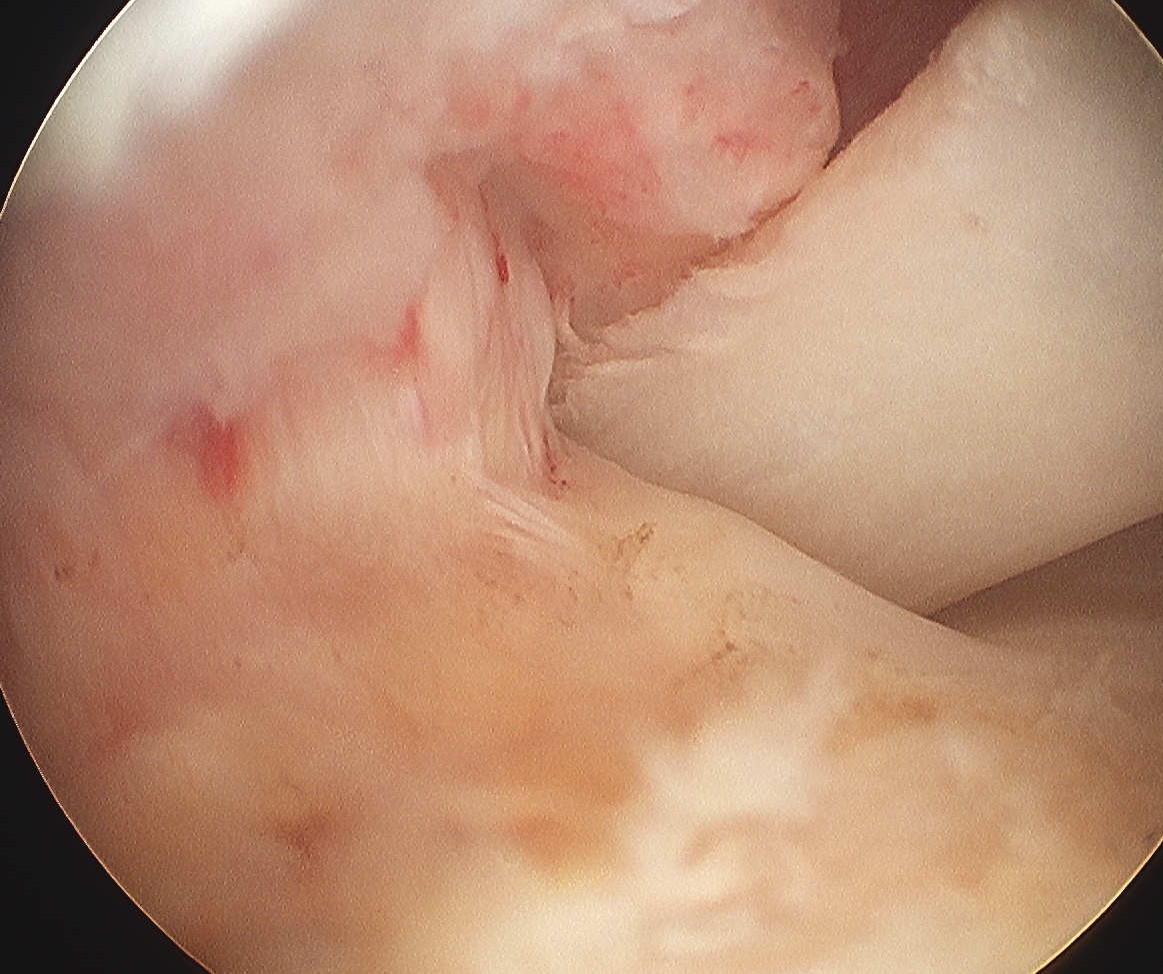

Bursal Sided

> 50% bursal sided tears with camer in subacromial space